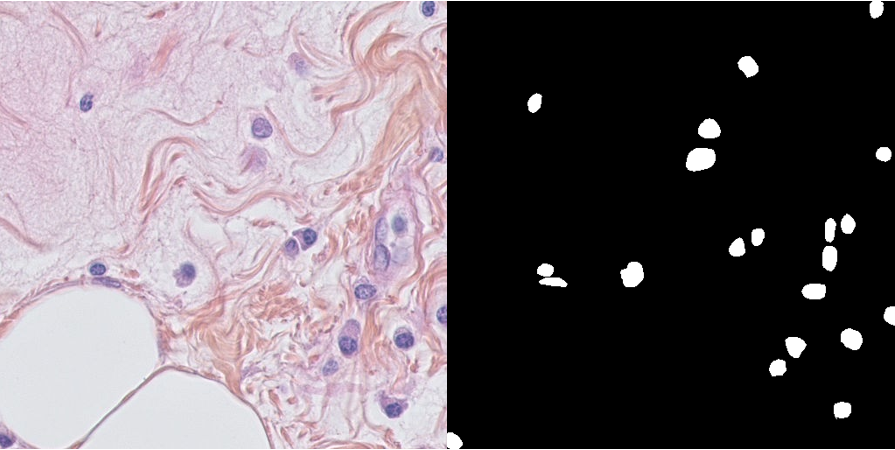

This dataset has been announced in the paper "Segmentation of Nuclei in Histopathology Images by deep regression of the distance map" in Transaction on Medical Imaging 2019.

This dataset consists of 50 annotated images, divided into 11 patients.

The dataset contains ground truth annotation for the segmentation of the nuclei.